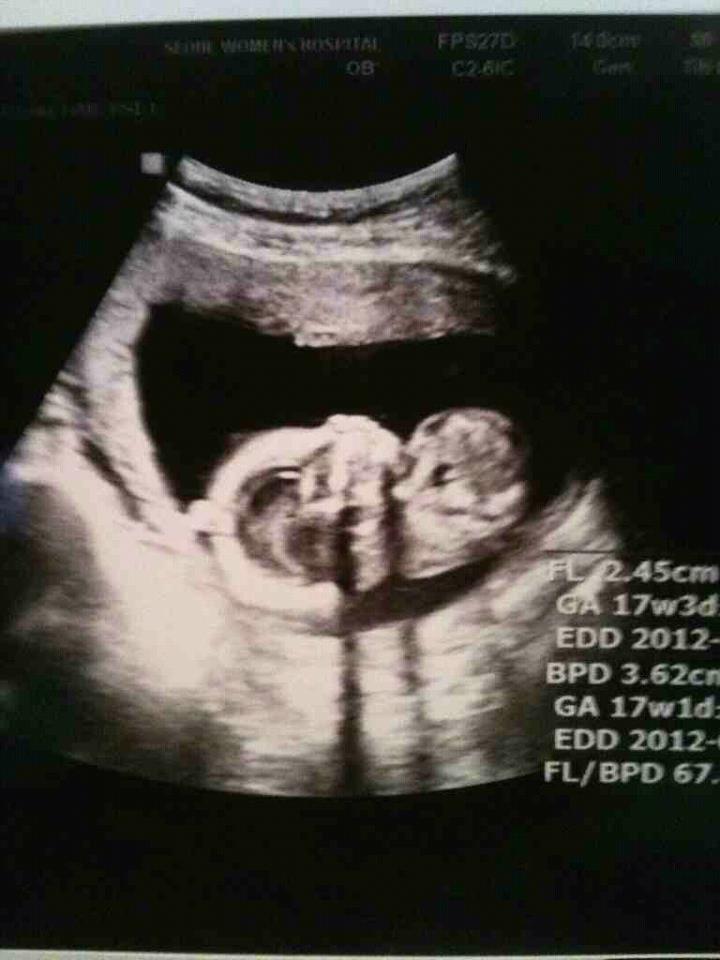

17ÁÖ µÈ  ¼ø¹é ¿·¸ð½À

Âü ½Å±âÇϱ⵵ ÇÏÁö

¾Æ°¡´Â °øÁÖ°í ¾ó±¼µµ ÀÛ°í ´Ù¸®°¡ ±æ´Ù°í Çß´Ù´Â ¾Æ°¡

¼ø¹é ¹ß¹Ù´Ú